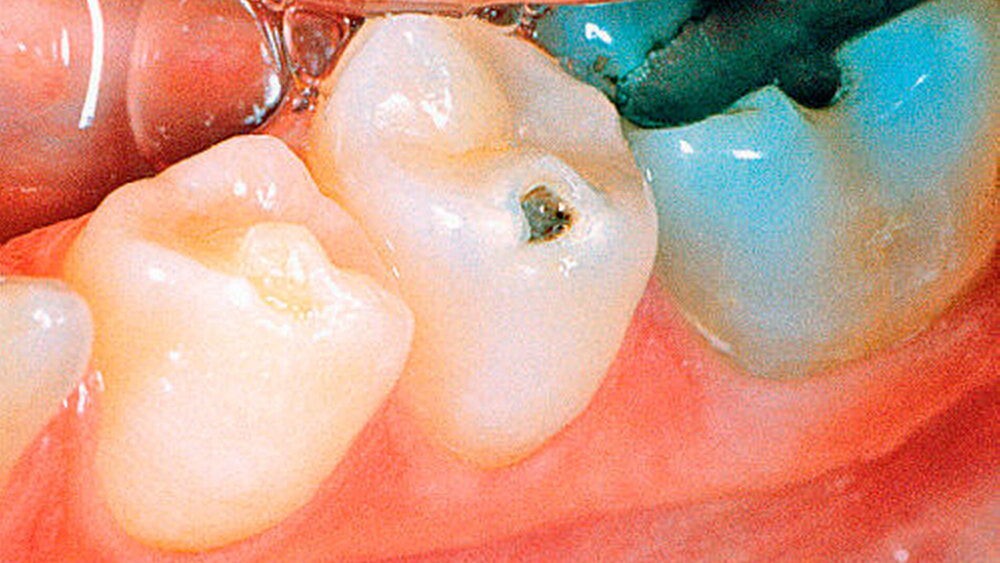

Zuerst bilden die vorhandenen Odontoblasten normales Dentin. Später werden die Odontoblasten zunehmend durch mesenchymale Zellen ersetzt, welche atypisches Dentin mit irregulär verlaufenden Dentintubuli bilden (Abbildungen 7a, b und 9). Die Dentinogenesis imperfecta führt zu einer blaubraunen Verfärbung der Milchzähne und zu einer bernstein-/perlmuttartigen Verfärbung der permanenten Zähne (Abbildungen 5, 6a,b und 8). Das vorhandene Dentin ist weicher als normal. Die histologischen Schnitte zeigen eine oft wellige Schmelz-Dentin-Grenze, was auf einen Defekt des Schmelz-Dentinverbundes schließen lässt (Abbildung 10). Infolge der mangelhaften Schmelz-Dentinverbindung splittert häufig Schmelz ab. Diese Schmelzabsplitterungen können zu Kariesbildung an atypischer Lokalisation führen (Abbildungen 6a, b). Zudem unterliegen die Zähne einer erhöhten Attrition. Irreguläre Dentinbildung kann nach dem Zahndurchbruch die gesamte Pulpakammer obliterieren. Beim gleichen Patienten können jedoch vollständig obliterierte neben normalen Pulpakammern beobachtet werden.